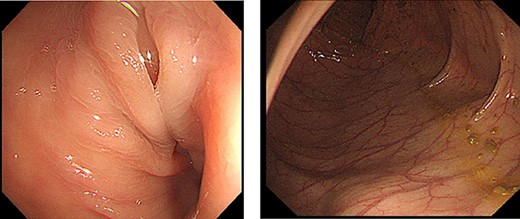

The transanal ileus tube was removed after the introduction of anesthesia. A 12-mm port was inserted at the umbilical site and insufflated for intra-abdominal observation. An additional 5-mm port was placed in the right midline for observation (Fig. 3).

Surgical findings. Twelve millimeter port was inserted at the umbilical site and an additional 5-mm port was placed in the right midline for observation.